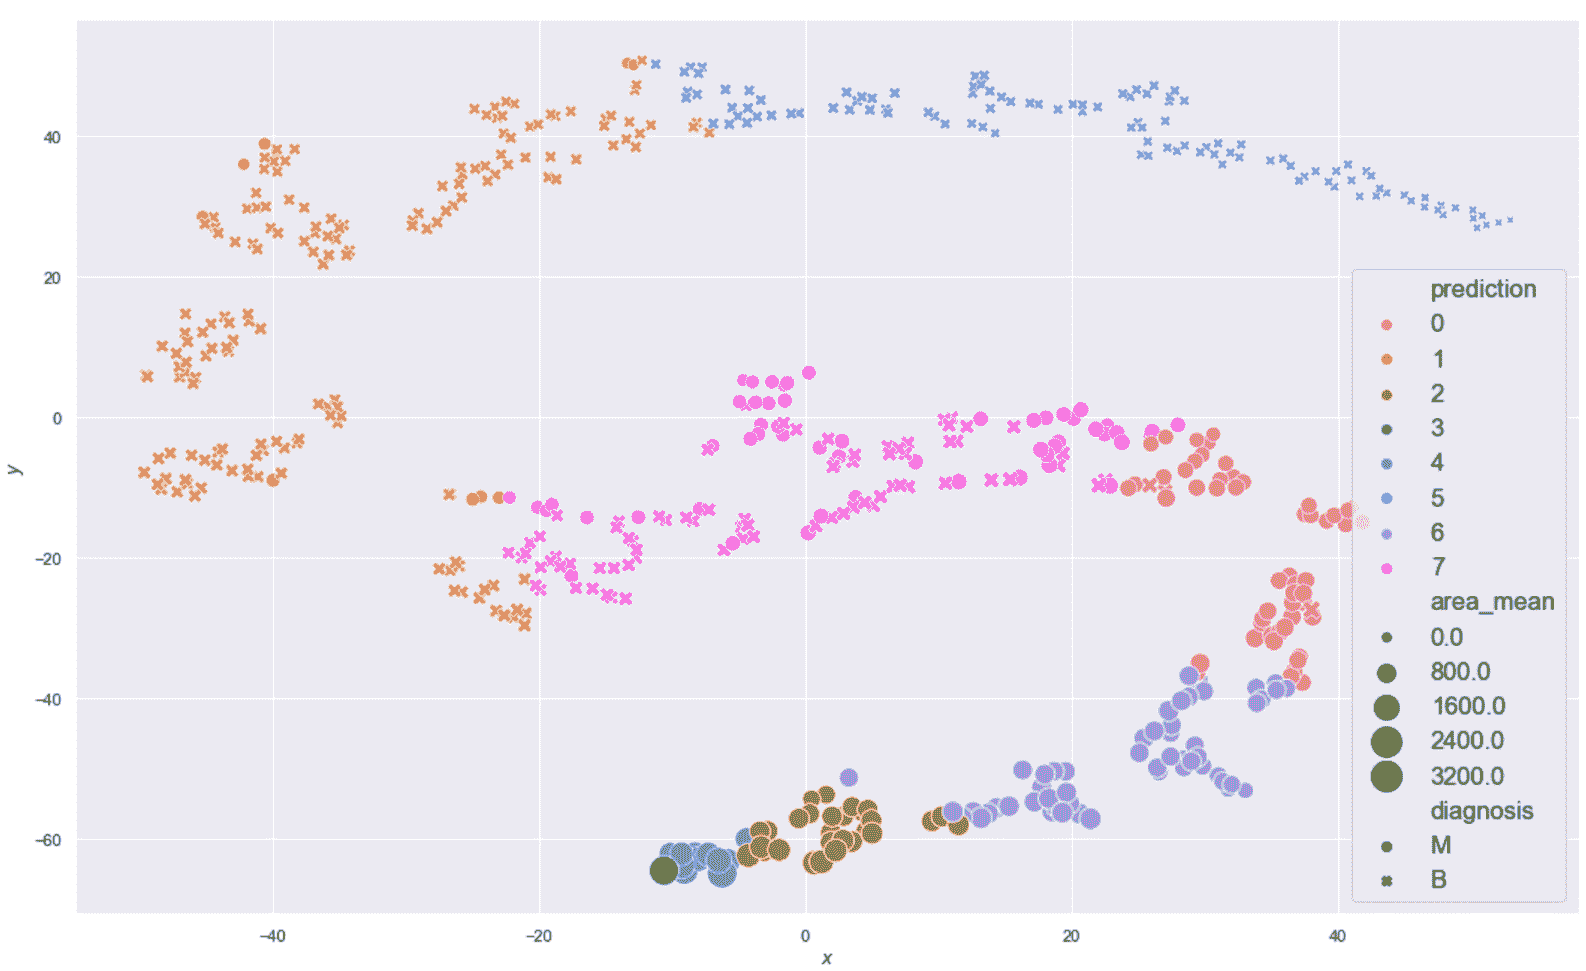

现在,我们在乳腺癌威斯康星州数据集上对八个聚类进行 K 均值聚类,以描述两个样本组, 的结构,如下所示

import pandas as pd

from sklearn.cluster import KMeans

km = KMeans(n_clusters=8, max_iter=1000, random_state=1000)

Y_pred = km.fit_predict(cdf)

df_km = pd.DataFrame(Y_pred, columns=['prediction'], index=cdf.index)

kmdff = pd.concat([dff, df_km], axis=1)

生成的绘图显示在以下屏幕截图中:

乳腺癌威斯康星州数据集的 K 均值聚类(K = 8)结果

现在,让我们考虑位于图底部的子群集(-25 < x < 30和-60 < y < -40) , 如下:

sdff = dff[(dff.x > -25.0) & (dff.x < 30.0) & (dff.y > -60.0) & (dff.y < -40.0)]

print(sdff[['perimeter_mean', 'area_mean', 'smoothness_mean',

'concavity_mean', 'symmetry_mean']].describe())

以下屏幕截图显示了统计表的打印友好版本:

恶性群集的统计描述

根据事实,我们知道所有这些样本都是恶性的,但是我们可以尝试确定一个规则。 area_mean / perimeter_mean之比约为9.23,相对于平均值,相对标准差非常小。 这意味着这些样本在非常狭窄的范围内代表了扩展的肿瘤。 而且,concavity_mean和symmetry_mean均大于总值。 因此(在不进行科学合理分析的前提下),我们可以得出结论,分配给这些群集的样本代表了已经进入晚期的非常糟糕的肿瘤。

为了与良性样本进行比较,现在考虑由x > -10和20 < y < 50界定的区域如下:

sdff = dff[(dff.x > -10.0) & (dff.y > 20.0) & (dff.y < 50.0)]

print(sdff[['perimeter_mean', 'area_mean', 'smoothness_mean',

'concavity_mean', 'symmetry_mean']].describe())

结果显示在以下屏幕截图中:

良性群集的统计描述

在这种情况下,比 area_mean / perimeter_mean 约为4.89,但是area_mean具有较大的标准差(实际上,其最大值约为410)。 concavity_mean相对于前一个非常小(即使具有近似相同的标准差),而symmetry_mean几乎相等。 从这个简短的分析中,我们可以推断出symmetry_mean不是判别特征,而concavity_mean的比值area_mean / perimeter_mean小于5.42(考虑最大值)。 小于或等于0.04应当保证良性结果。 由于concavity_mean可以达到非常大的最大值(大于与恶性样本相关的最大值),因此有必要考虑其他特征,以便确定是否应将其值视为警报。 但是,我们可以得出结论,说属于这些群集的所有样本都是良性的,错误概率可以忽略不计。 我想重复一遍,这不是真正的分析,而是更多的练习,在这种情况下,数据科学家的主要任务是收集可以支持结论的上下文信息。 即使存在基本事实,该验证过程也始终是强制性的,因为根本原因的复杂性可能导致完全错误的陈述和规则。